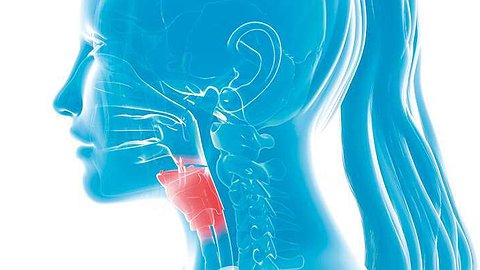

Гортань – это особый, единственный орган, который объединяет в себе две жизненно важные функции: дыхательную и пищеварительную. Гортань является передней стенкой глотки, а надгортанник перекрывает трахею во время приёма пищи, что не позволяет человеку задохнуться или поперхнуться. Когда из-за онкологического заболевания удаляется гортань, человек теряет возможность принятия пищи. Рак гортани не является лидирующим заболеванием в России, тем не менее в год им заболевают более 7000 человек. И с каждым годом заболеваемость растёт. И причина этого – факторы риска.

Когда пациент приходит ко мне на приём, первое, что спрашиваю: вы курите? Выпиваете? Это не праздное любопытство, а то, что нужно знать до начала лечения. Алкоголь и курение, работа в условиях повышенной запылённости, носительство вируса папилломы человека и Эпштейна-Барр, а также неправильное питание значительно увеличивают риски развития рака гортани.